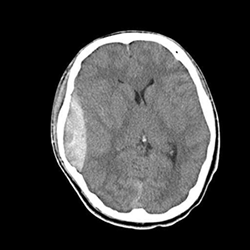

急性水頭症の具体例

急性水頭症では、脳室が拡大して頭蓋骨の内側の圧力が高まり、激しい頭痛、嘔吐、意識障害などが生じます。

さらに、脳室の拡大による圧迫が脳ヘルニアの状態まで進行すると、深部にある脳幹が侵されて呼吸障害などを生じ、最悪の場合には死に至ります。

急性水頭症に対しては、脳室ドレナージ術を緊急で行います。局所麻酔をかけて頭蓋骨に小さな孔をあけ、脳室にチューブを挿入します。脳脊髄液とともに、脳室内の出血を取り除きます。

画像の中央部に白く細長い像がありますが、これは、脳室内出血を抜き取るためのドレインチューブが映ったものです。